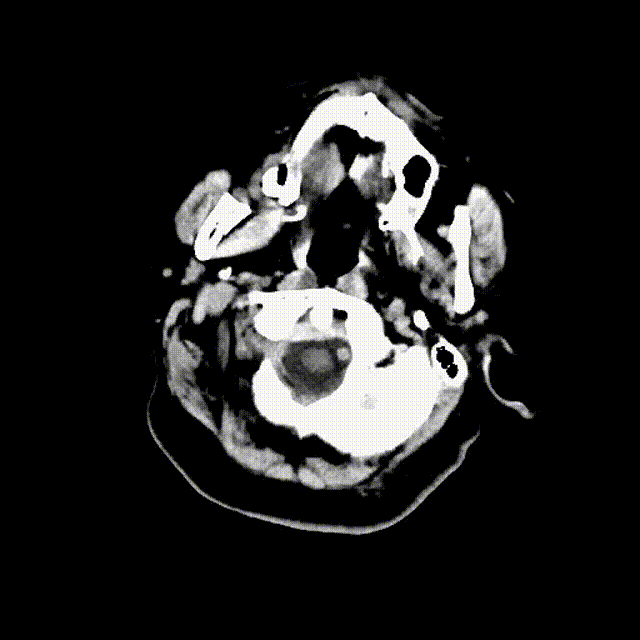

术前造影

右侧椎动脉造影见代偿右侧前循环供血

左侧椎动脉造影